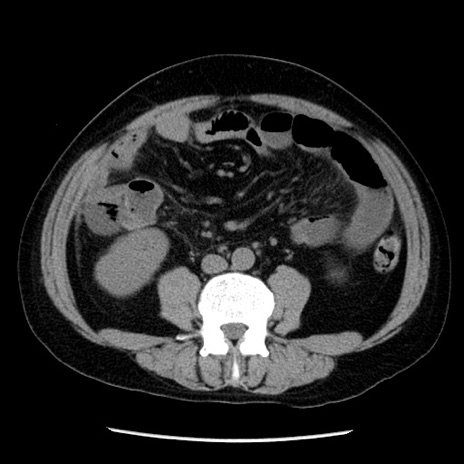

冠状断像

【症例】40歳代男性

【現病歴】2日前から胃痛あり。徐々に周期的な激痛に変化した。本日になっても激痛があるため受診。

【身体所見】意識清明、BT 38-39℃台あり、腹部:膨満、やや硬、右下腹部に圧痛あり。

【データ】WBC 8500、CRP 23.26